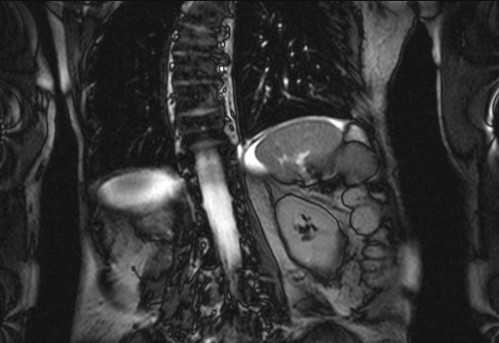

Auffälliges Abdomen bei der Vorsorgeuntersuchung einer älteren Dame

ICD: C64

68 Jahre alte Frau. Sie geht zur Darmspiegelung im Rahmen ihrer Krebsvorsorgeuntersuchung. Der Internist bemerkt bei der ergänzenden sonografischen Untersuchung des Abdomens einen auffälligen Befund.